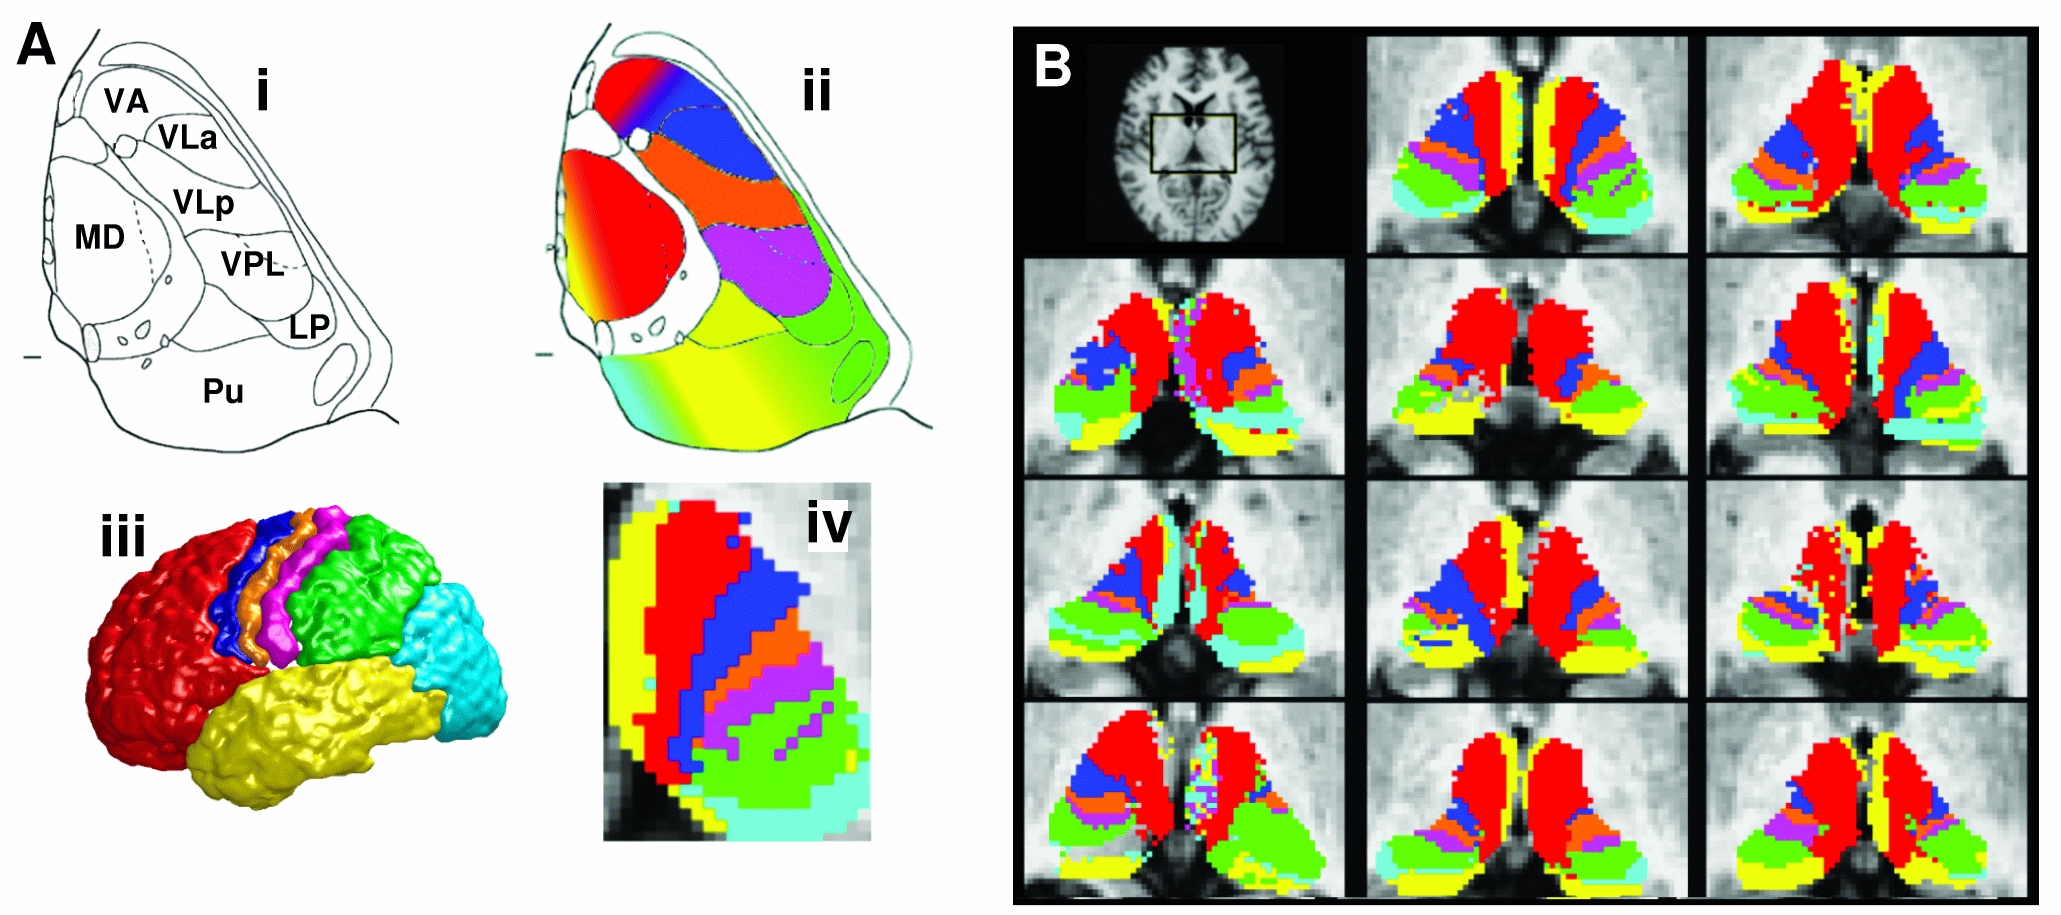

Classification targets

When using classification targets, probtrackx will quantify connectivity values between a seed mask and any number of user-specified target masks. This option is only active when the seed mask is a single mask. In the example on the right, seed voxels in the thalamus are classified according to the probability of connection to different cortical target masks.

Use the add button to locate each target mask. Targets must be in the same space as the seed mask. When all targets are loaded you can press the save list button to save the list of targets as a text file. If you already have a text file list of required targets (including their path) then you can load it with the load list button. The output directory will contain a single volume for each target mask, named seeds_to_{target} where {target} is replaced by the file name of the relevant target mask. In these output images, the value of each voxel within the seed mask is the number of samples seeded from that voxel reaching the relevant target mask. The value of all voxels outside the seed mask will be zero. Note that the files seeds_to_{target} will have the same format (either volumes or surfaces) as the seed mask.

There are command line utilities that can be run on these outputs:

- proj_thresh - for thresholding some outputs of probtrackx

- find_the_bigggest - for performing hard segmentation on the outputs of probtrackx, see example on the right

find_the_biggest

find_the_biggest is a command line utility that performs hard segmentation of a seed region on the basis of outputs of probtrackx when classification targets are being used.

The output of Connectivity-based seed classification is a single volume for each target mask, named seeds_to_{target} where {target} is replaced by the file name of the relevant target mask. In these output images, the value of each voxel within the seed mask is the number of samples seeded from that voxel reaching the target mask. find_the_biggest classifies seed voxels according to the target mask with which they show the highest probability of connection. It is run as follows:

find_the_biggest <list of volumes/surfaces> <output>

Where the list of volumes is the outputs of Connectivity-based seed classification (i.e., files named seeds_to_target1 etc etc).

The example below uses probtrackx and find_the_biggest to perform hard segmentation of the thalamus on the basis of its connections to cortex.